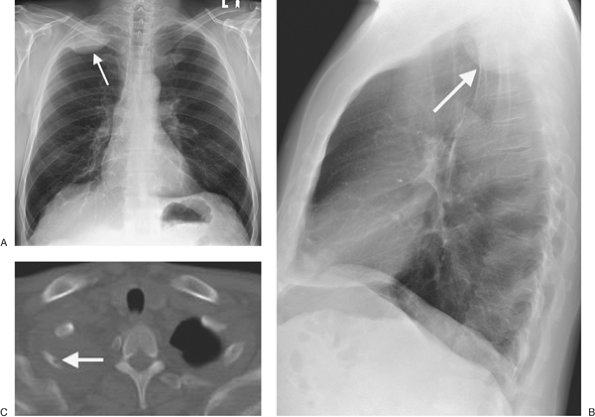

FIGURE 9-4. Pancoast tumor. PA (A) and lateral (B) chest radiographs of a 61-year-old man with right shoulder pain and a 40–pack-year history of cigarette smoking shows a circumscribed mass (arrow) in the right apex. C: CT with bone windowing shows the mass filling the right lung apex and destruction of the right second rib (arrow).

root of the right lung, between the pericardium and mediastinal pleura. The left phrenic nerve descends between the left subclavian and left common carotid arteries, lateral to the vagus nerve and the arch of the aorta. It passes in front of the root of the left lung between the mediastinal pleura and the pericardium, and its branches pierce the diaphragm immediately to the left of the pericardium. Tumor invading the phrenic nerve on either side can result in elevation of the ipsilateral diaphragm and should always be considered as the cause of an abnormally elevated diaphragm in patients over age 35 unless proven to be stable for 2 years or more on prior chest radiographs (Fig. 9-44). The chest radiograph may not show the tumor itself, and occasionally the elevated diaphragm may be the only radiographic clue to an underlying neoplasm.

FIGURE 9-44. Bronchogenic carcinoma invading the phrenic nerve. A: PA chest radiograph of a 74-year-old woman shows normal positioning of the hemidiaphragms. B: PA chest radiograph obtained 1 year later shows elevation of the right hemidiaphragm and no evidence of mediastinal mass. C: CT shows a homogeneous soft tissue mass adjacent to the superior vena cava (arrows), which proved to be a bronchogenic adenocarcinoma invading the right phrenic nerve. This case illustrates the significance of new diaphragmatic elevation in an adult, even when no mediastinal mass is seen on the chest radiograph.